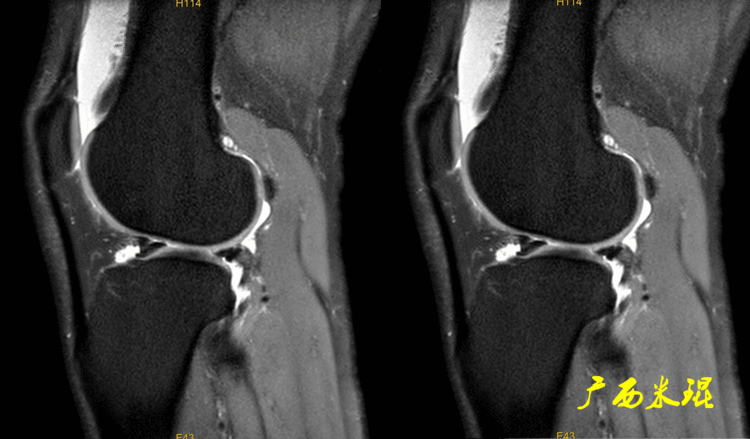

如同下面这张MR,左侧图像为手术前的,右侧图像为手术后的,术后病人疼痛等症状仍然存在,复查MR见外侧半月板前角分层,半月板前角的处理是有一定难度的,有经验的医生会考虑可能是手术者对前角的处理不够熟悉,没有通过另外的办法处理半月板前角的水平裂,不过也只能是猜测而已。所以,对于半月板术后的评估,症状的消失比MR重要!